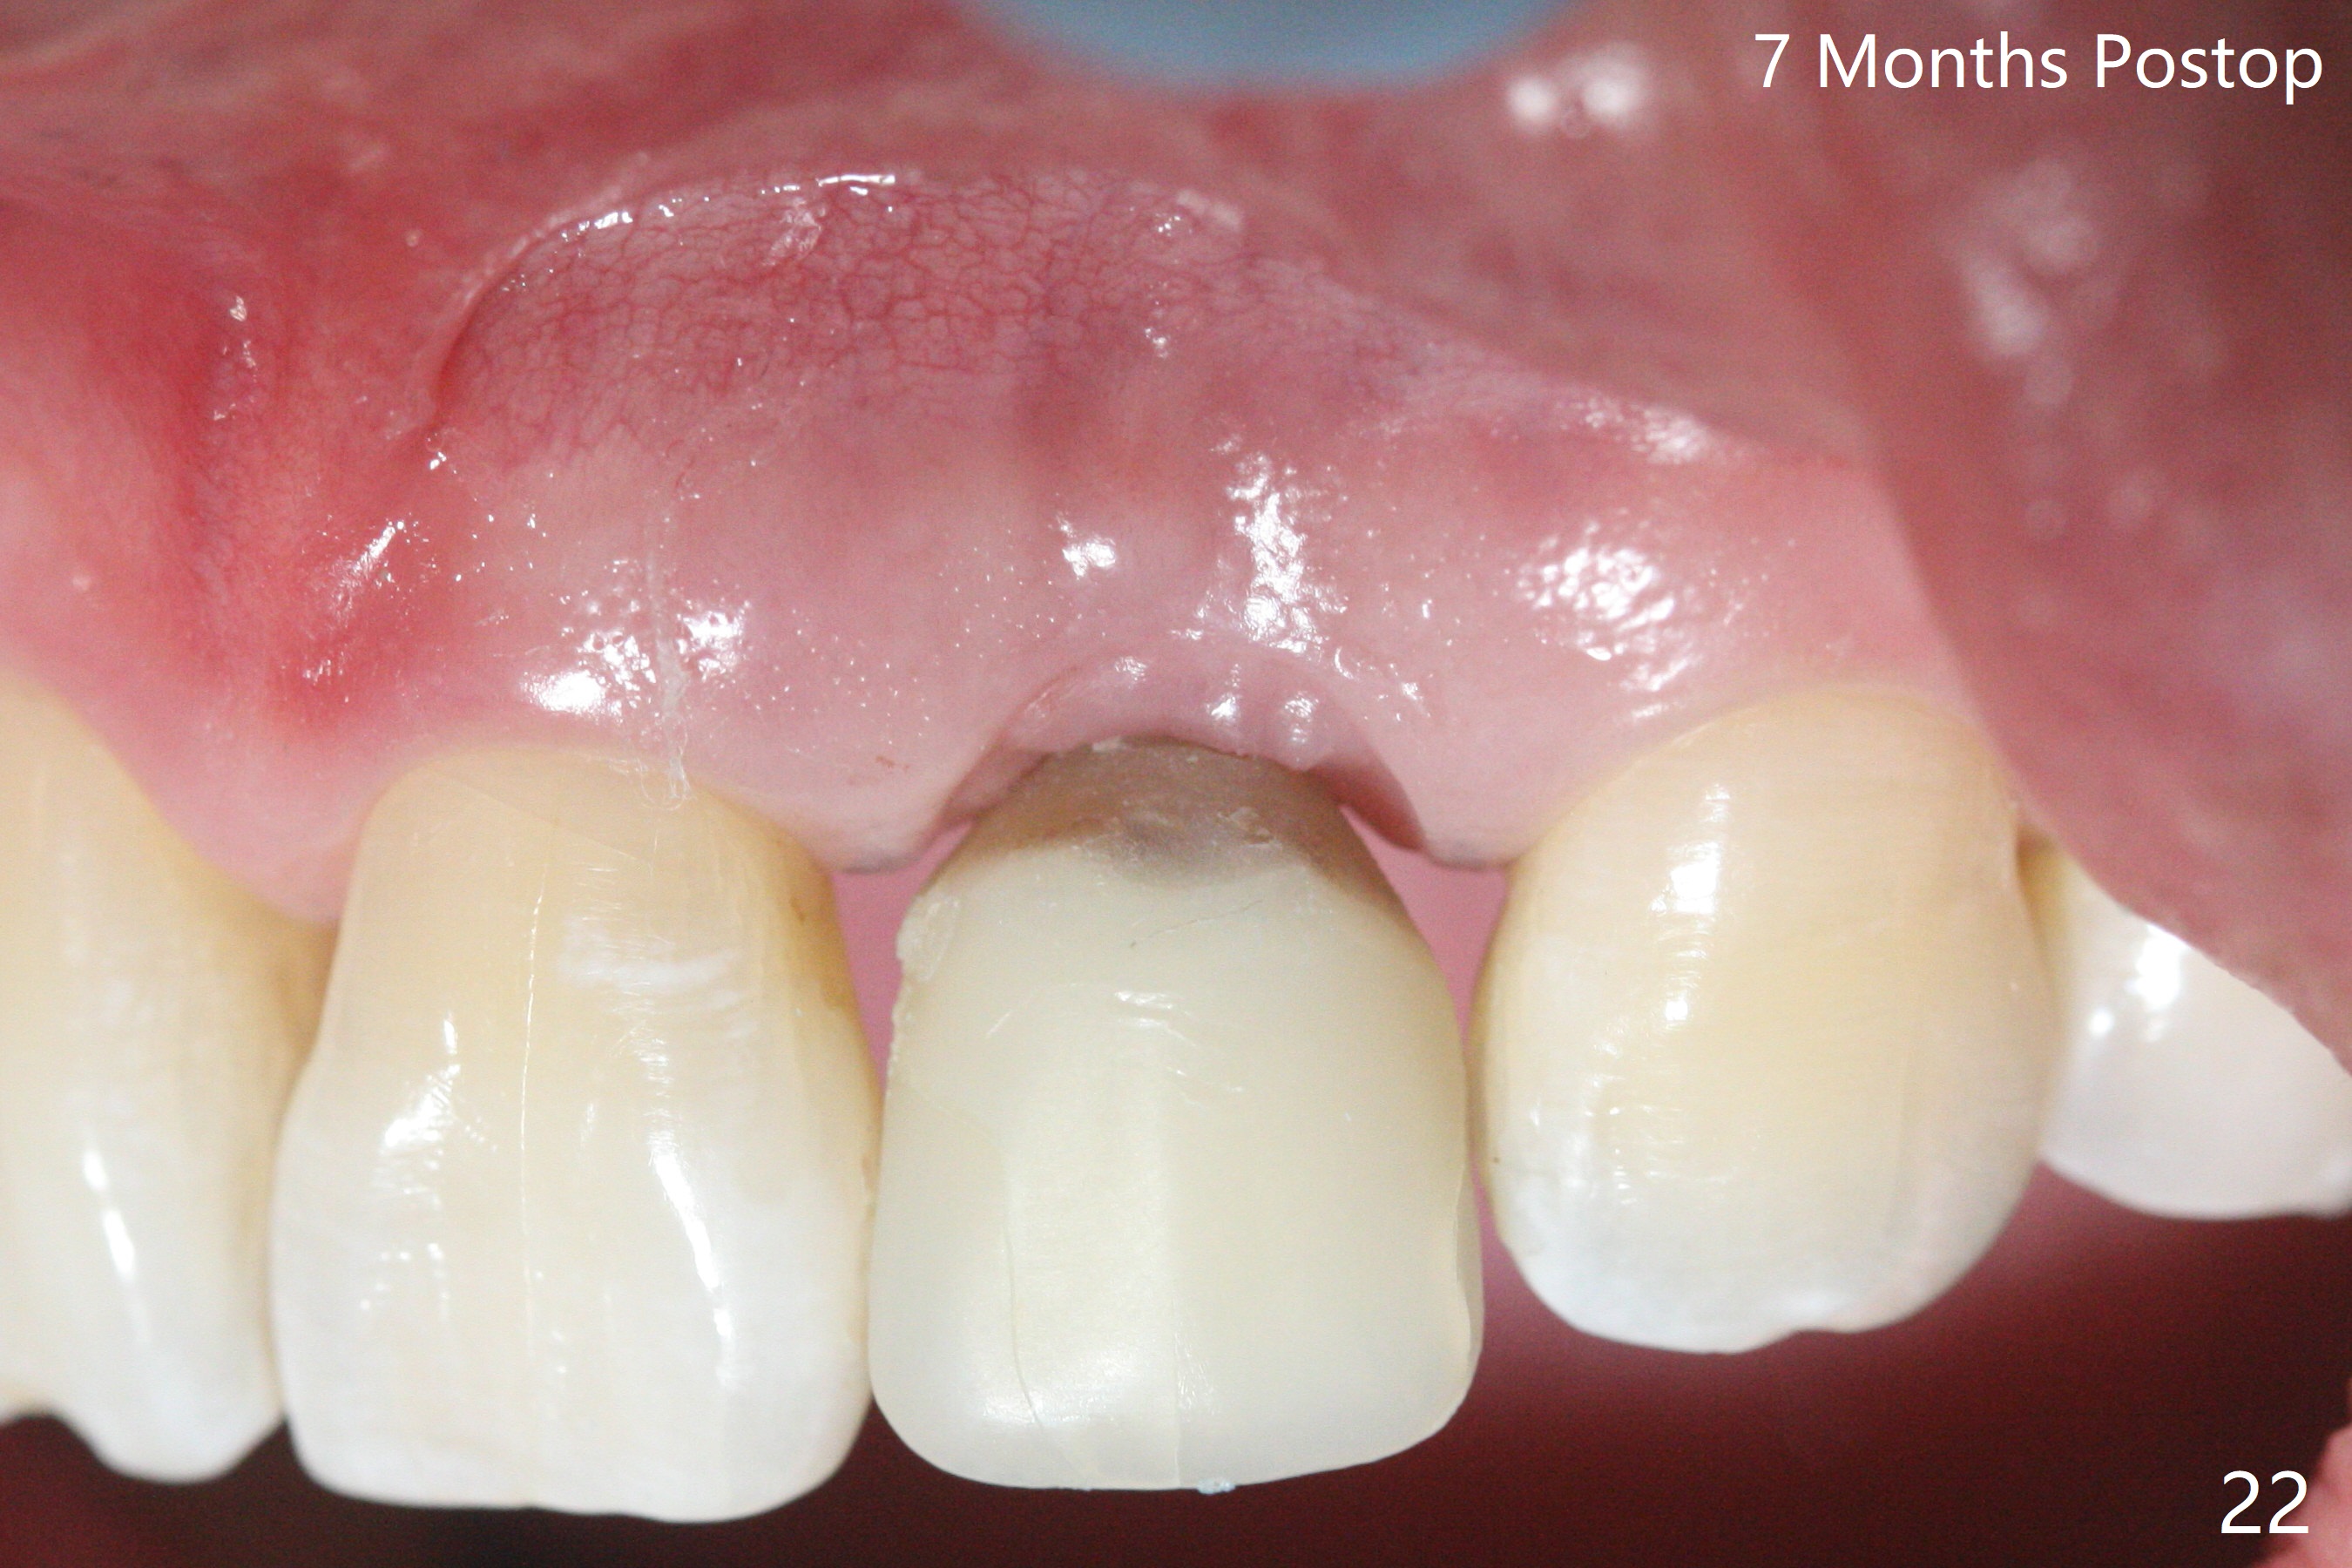

病人回来带来瘘道(图一),不过不会增加难度,病牙去除,它便自动消失。尽管颊侧骨壁完全失去,颊侧牙龈仍丰满(图二),为什么呢?第一,因为粗大牙根存在,第二两旁牙齿,牙槽骨撑着帐篷(侧切牙颊侧牙龈),第三,牙冠。为了防止术后牙龈塌陷,尽量不切开,即刻放置植体(牙根);由于前牙缘故,这次植体不能很大,所以植骨必须过度(over grafting),最后即刻制作临时牙冠,撑住牙龈。这就是所谓每个人进入角色。这个牙根有一种先天性畸形:dens in dent (图三(腭侧观):箭头)。尽管腭侧牙根畸形,腭侧骨壁吸收临床上并不严重,所以钻洞仍偏腭侧。当预定最后钻头还在钻洞时,填入大量粘性骨块(图四:*),细长植体还没有完全卡入鼻底(图五),最后好像可以(图六,七)。植体,骨粉入位(图八),最后临时牙冠出场(图九)。尽管植体小,术后一周临时牙冠仍然可以维持牙龈原有形状(emergency profile,图十:箭头(*:树脂强化牙冠固定))。图十一以不同角度显示瘘道缩小。术后三周取出有些松动的临时牙冠,骨粉虽然还没有被肉芽组织整合,但是显得正常,周围牙龈健康(图十二)。术后4个月牙龈形态正常(图十三),没有触痛;颊侧骨板轻度凹陷(图十四);骨粉仍在原位(图十五)。术后7个月骨粉仍在原位(图十五,十六,但是冠部密度减低(可能骨粉流失,需要牙周或者树脂敷料保护)),没有螺纹暴露。但是牙冠边缘暴露,说明牙龈收缩(图十七,与图十三对比),颊侧骨板仍塌陷(图十八)。插入龈线取得多个目的:修整基台边缘,取模,颊侧牙龈推向颊侧,有利于即将衬里牙冠龈缘进入龈下(图十九)。取模后牙冠边缘(图二十:<)衬里,然后修整,变窄,以便插入龈下,促进颊侧牙龈下降(图二十一,二十二)。术后8个月牙冠粘固前牙龈健康(图二十七,八),牙冠(图二十九)固位后,病人满意(图三十),咬合调整(图三十一),注意腭侧粘固粉流出通道(<)。